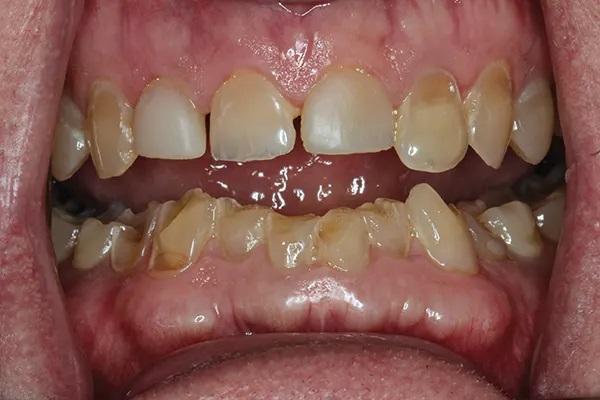

Мужчина, 54 года, был направлен к автору по поводу истирания зубных рядов и эрозии, которые, как предполагалось, были вызваны выраженным бруксизмом (Фото 1 и Фото 2). Его лечащий врач не был уверен, с чего начать планирование лечения, из-за предполагаемой сложности случая. Основной проблемой пациента был страх потерять часть или все зубы из-за обширного разрушения эмали (Фото 3). Были собраны снимки и подробные медицинские и стоматологические истории болезни, а также проведено детальное клиническое обследование. Полные снимки, фотографии и цифровые сканы были отправлены в зуботехническую лабораторию, и был разработан план лечения. У пациента было сильное желание действовать, и он принял этот план. Клинический случай был разбит на сегменты для обеспечения предсказуемой и более удобной реконструкции.

Фото 1: Фото улыбки анфас до лечения. Пациент хотел сохранить свои зубы и улучшить свою улыбку.